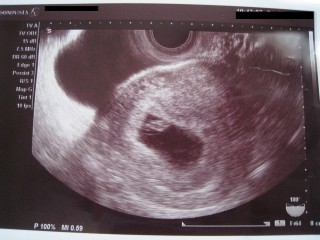

一度流産したのですが、それから自分なりに切り替えて旅行に行ったりしてリフレッシュできた頃、二度目の妊娠。6w6dで初診し胎嚢、胎芽、卵黄のう、心拍まで確認できました。生まれてくるまでハラハラ不安ですが、信じて楽しみに待っています!

6w6dでの検診で、卵黄嚢と赤ちゃんと心拍が確認出来ました。 心臓がチカチカ、ピコピコと動いていて感動しました! 赤ちゃんの大きさは0.72cmです。 つわりで本当にツライけど頑張らなきゃ!と思いました。